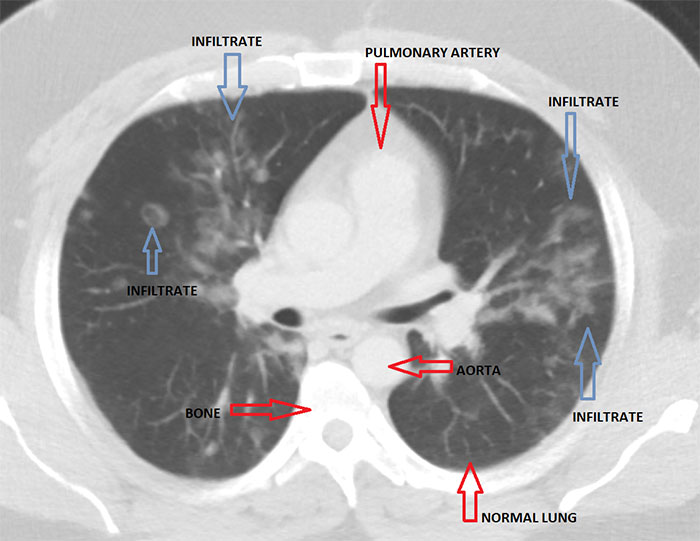

Imgur user and radiologist HeyYoMikey8 said the unknown future is the hardest part of the coronavirus pandemic. HeyYoMikey8 believes it is our own responsibility to educate ourselves so we can all do our part during these difficult times. So, to make it easier for us, the health professional shared what they’re seeing in cases of Covid-19 radiographically. The comprehensive commentary, as well as images used to help in the diagnosis and managing complications or evaluating the progression of the disease, should definitely broaden your understanding of what we’re all facing.

Interestingly, in the early days of the coronavirus outbreak, radiological imaging was not regarded as a way to confirm evidence for COVID-19 cases. Instead, authorities relied on a positive result of the PCR nucleic test. The supply of the PCR test kits, however, was limited and getting back the results took a long time. So, Chinese health authorities soon recognized these difficulties and changed the diagnostic strategy in their 5th edition of the Guidelines on Diagnosis and Treatment of COVID-19. As a result, radiological features of COVID-19 were included as one of the three determinant clinical manifestations to confirm a suspicious patient. The high efficiency, reliability, and accessibility of the radiological diagnostic technology have helped tremendously in identifying the disease. These processes were soon enhanced further by the introduction of artificial intelligence (AI) algorithms.

This could mean CT scanners were to be shut down for up to an hour after a single scan, severely limiting throughput for other patients including for emergent indications like trauma. “The radiology technologists are the real unsung heroes in all of this as they have to deal directly with many potentially infected patients to get their imaging done timely and appropriately, and should be seriously commended right now. We face problems with the diagnosis because a negative study does not rule out the disease, as it may have not yet manifest as an infiltrate despite the infection being present (false-negative scans).”

“Secondly, although certain concerning patterns suggesting COVID-19 on imaging have emerged, all findings are strictly nonspecific and therefore do not entirely rule in the diagnosis, and require additional confirmation as it could still be other entities such as Influenza pneumonia.”

“Finally, all radiology is a business like any other, and we have canceled or deferred almost all elective imaging procedures to help stall the spread of infection and make room for a potential surge of COVID-19 cases,” the radiologist explained. “Therefore, our imaging volumes have dropped by upwards of 50% basically overnight, leaving us with a lack of work for our normal staffing (requiring forced vacations) and a large dip in revenue which jeopardizes our ability to pay the bills and keep our nonphysician employees employed and paid. I do think radiology has helped us at least in this early stage to identify many presumptive cases that were not being considered as COVID-19 at their presentation … It may be helpful for follow up evaluation for potential complications such as ARDS or pleural effusions. Also, there are patients with respiratory symptoms now concerning COVID-19 that have imaging findings/patterns more consistent with other etiology such as bacterial pneumonia or pulmonary embolism, therefore helping to rule out many cases and guiding other appropriate treatment.”